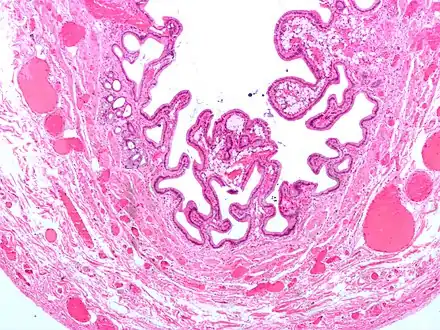

Micrograph of cholesterolosis of the gallbladder

The name strawberry gallbladder comes from the typically stippled appearance of the mucosal surface on gross examination, which resembles a strawberry. Cholesterolosis results from abnormal deposits of cholesterol esters in macrophages within the lamina propria (foam cells) and in mucosal epithelium. The gallbladder may be affected in a patchy localized form or in a diffuse form. The diffuse form macroscopically appears as a bright red mucosa with yellow mottling (due to lipid), hence the term strawberry gallbladder. It is not tied to cholelithiasis (gallstones) or cholecystitis (inflammation of the gallbladder).[2]